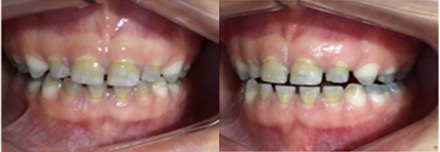

Luego de un año y dos meses, el paciente volvió al consultorio para control. Los dientes presentaban una coloración mucho más clara, principalmente, los incisivos superiores e inferiores. Pudimos observar también en la superficie oclusal de los molares inferiores un área de completa despigmentación (Figuras 4 y 5).

Figura 4: Control- 1 año. Imagen vestibular de los dientes. Se observa pigmentación verde más clara en los incisivos superiores e inferiores.

(A) Frontal y (B) Lateral izquierda

Figura 5: Control 1 año. Imagen oclusal de los dientes. (A) Oclusal inferior y (B) Oclusal superior. Se observa pigmentación verde. Pigmentación más clara en los molares y caninos superiores e inferiores